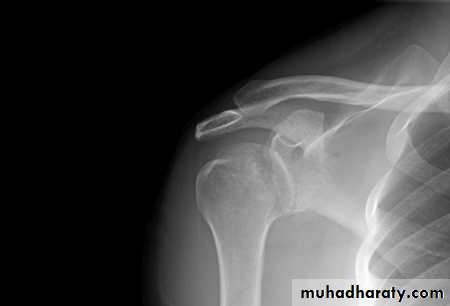

X-rays

frcature spine and peripheral nerve

should be obtained to exclude fractures of

the shoulder or clavicle (which are not uncommon

and which can be mistaken for obstetrical palsy).